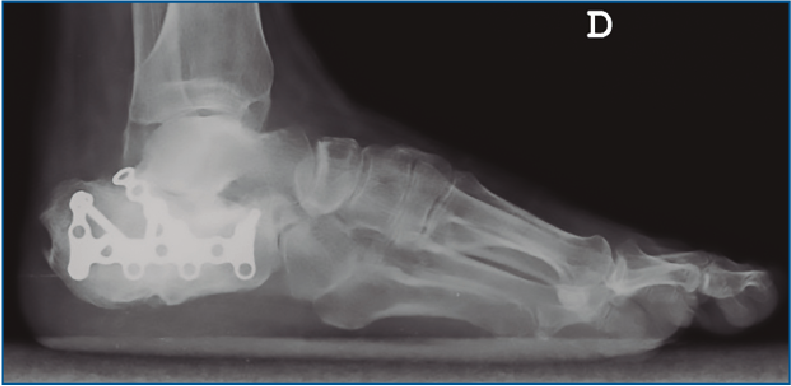

En aquellos a quienes se les planteó cirugía abierta se usó una vía de abordaje lateral extendida en “L” con una incisión ligeramente curva a nivel de la zona posteroinferior del calcáneo para evitar un ángulo recto y la necrosis apical del mismo. Se utilizó osteosíntesis con placas de tipo LCP (Figura 1) y, en casos clasificados como Sanders IV, artrodesis subtalar realizada con 2 tornillos canulados de 6,5 mm. El comienzo aproximado de la carga ha sido entre las 10 y las 12 semanas.

Figura 1. Reducción abierta fijación interna mediante placa tipo LCP. Vía de abordaje lateral en “L”.